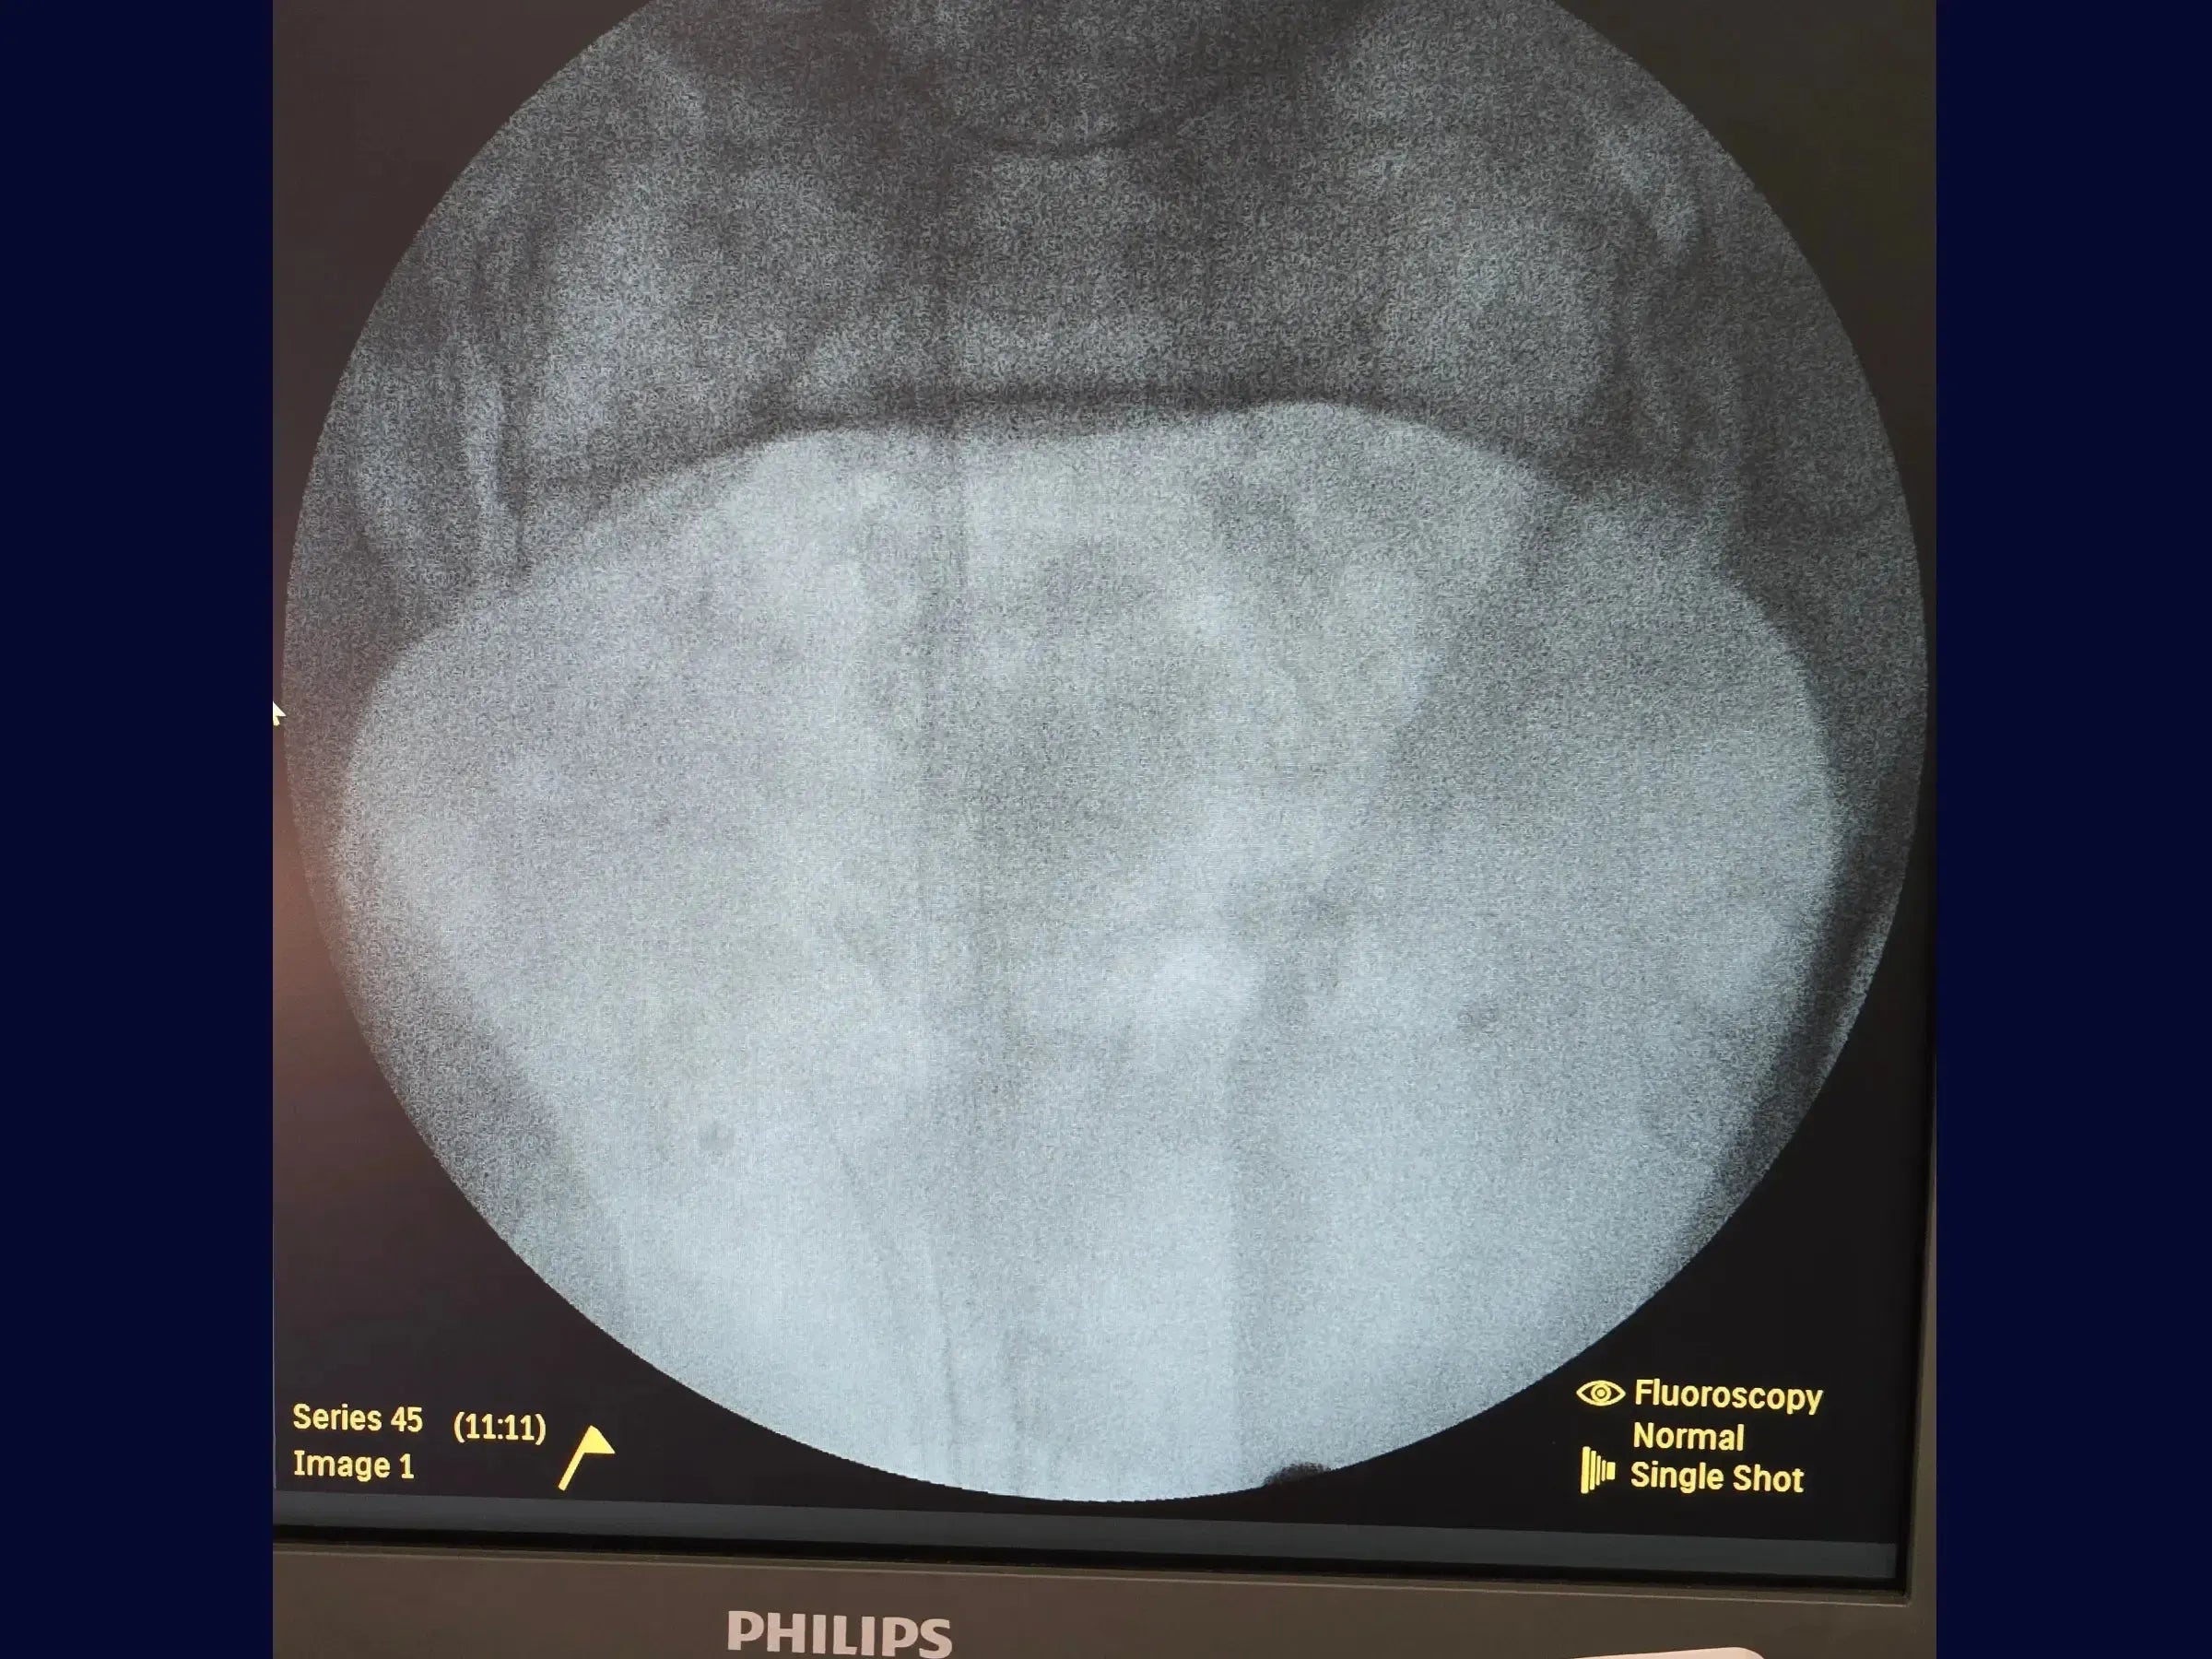

- Posicionamento e Acesso: Posicione o paciente em decúbito dorsal para acesso livre do intensificador de imagem. Realize uma incisão aproximadamente 2 cm superior à sínfise púbica, expondo a fáscia do reto femoral e a linha alba. Faça uma incisão longitudinal na linha alba e localize o tubérculo púbico.

- Redução Provisória: Utilize parafusos temporários, um de cada lado da sínfise, inseridos de anterior para posterior com medição precisa. Empregue uma pinça específica acoplada a esses parafusos para redução e ajuste, controlando o cisalhamento e abertura visualmente.